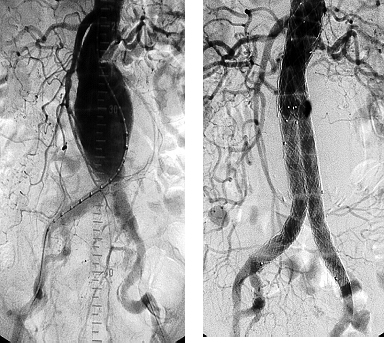

腔内介入治疗

自1991年Dr.Parodi在临床上第一次报道腹主动脉瘤行直型覆膜支架植入术以来至今腔内介入治疗已逾30年历史,技术日臻成熟。其基本原理是将带膜支架释放固定于病变主动脉两端的正常主动脉上,血流即从支架腔内流过,病变扩张的薄弱腹主动脉壁即与高速高压的腹主动脉血流隔绝,这样既维持了腹主动脉的血流通畅又达到了预防腹主动脉瘤破裂的目的,也就是说完全治愈了腹主动脉瘤。腹主动脉瘤虽然凶险,但随着医疗技术的日新月异,使得罹患腹主动脉瘤的患者的死亡率和并发症大幅度降低。与绝大多数疾病一样,腹主动脉瘤能取得满意的预后最关键的因素之一就是早发现早治疗。因此,增强自身健康意识、体检意识非常重要,尽早发现“不定时炸弹”,及时取得血管外科专科医生的诊疗意见,必要时拆除“炸弹”,这样才能使我们获得更加幸福美满的生活。